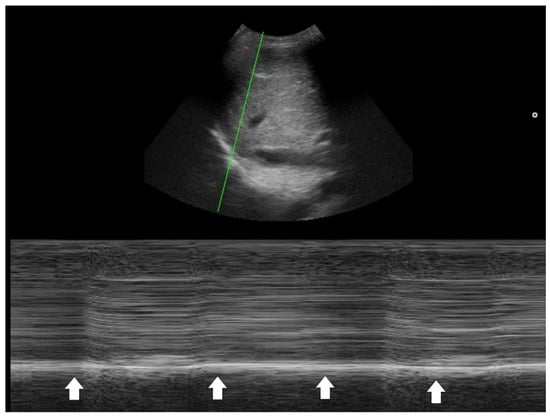

One key clinical implication of PSI and CURB-65 is the prognostic value of comorbidities, physical signs, and laboratory data in CAP. PoCUS serves as a powerful tool to detect occult co-morbidities—such as heart failure, chronic kidney disease, and liver disease—that are incorporated into the PSI score [32]. Laboratory items in PSI and CURB-65 aim to identify signs of sepsis. In this context, PoCUS can help confirm a hyperdynamic left ventricle in patients with tachycardia and/or hypotension [40,41,42], or a hyperdynamic diaphragm in tachypneic patients as a compensatory response [43,44]. Suboptimal diaphragmatic excursion in a patient is an ominous sign, indicating poor respiratory endurance and limited reserve (Figure 4) [45,46,47,48].

Figure 4. M-mode tracing of the diaphragm (green line indicates the scanning line) showed minimal respiratory excursion (arrows), indicating poor diaphragm function.